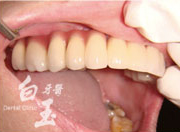

治療後